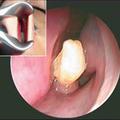

V nosu mu je rasel zob

Nenavaden vzrok neprestanega krvavenja iz nosu. V nosni votlini mu je zrasel zob.